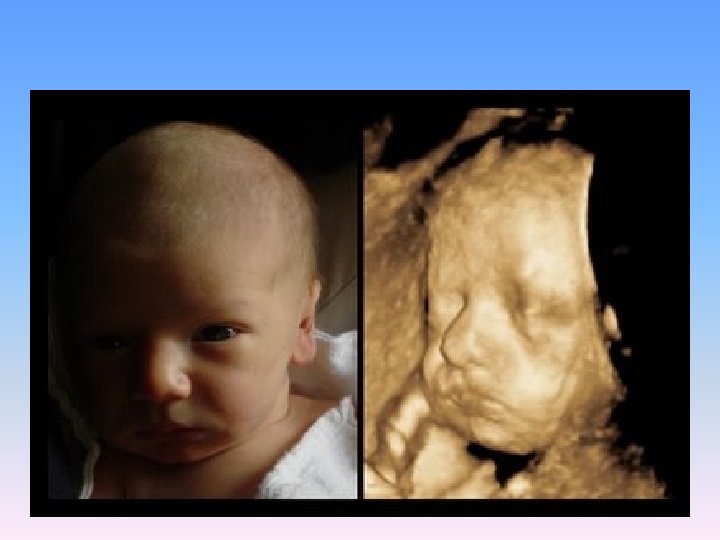

2 -D

3 -D and 4 -D National Geographic Channel In The Womb